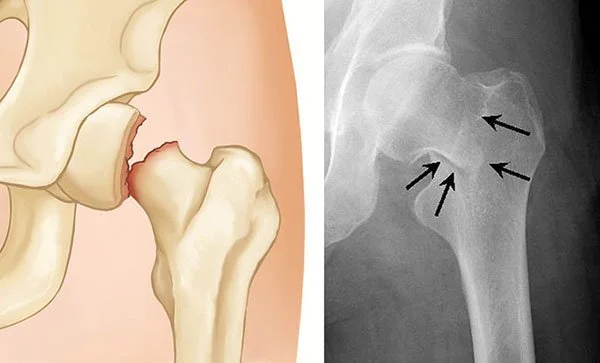

X-ray images of a hip joint; the left shows a normal joint space and the right shows joint space narrowing.

Hip Arthritis (Total Hip Replacement)

Hip arthritis can cause severe pain, stiffness, and loss of mobility. When non-surgical treatments no longer provide relief, total hip replacement replaces the damaged joint surfaces with smooth, durable implants that restore motion, relieve pain, and help you get back to an active life.